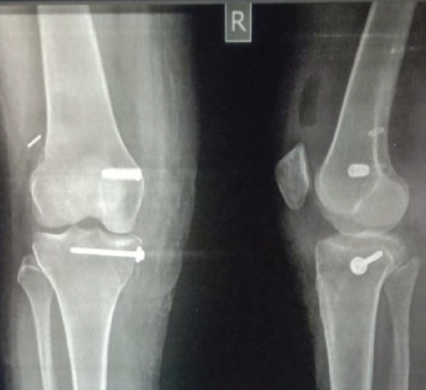

The optimal timing for surgery remains a subject of ongoing debate. Our findings are consistent with those of Harner et al. [6] and Mook et al. [19], as well as the recent meta-analysis by Vaishya et al. [24,32], support early reconstruction – ideally within 3 weeks – to facilitate graft placement and reduce arthrofibrosis risk. However, in cases with severe soft tissue compromise or delayed presentation, often seen in rural LMIC contexts, delayed surgery may be unavoidable. Yoon et al. [8] highlights that while delayed intervention can still yield acceptable results, early timing is associated with faster neuromuscular recovery. In our cohort, single-stage reconstruction yielded excellent functional outcomes without increasing complication rates, aligning with the findings of Ishibashi et al. [5] and Joutoku et al. [4]. Recent systematic reviews [26,29] indicate that single-stage procedures reduce hospital stay, rehabilitation time, and costs – critical advantages in LMIC settings. Staged approaches remain indicated for cases with severe swelling, vascular repair, or open injuries [14,16], but their higher rehabilitation demands and resource implications make them less feasible in many environments. Graft selection remains a critical factor in MLKI reconstruction. The STG autografts were our primary choice; PL autografts were used when the quality of the hamstring was found to be suboptimal, a finding also supported by Goyal et al. [10]. Moreover, a recent systematic review [31] demonstrates comparable biomechanical strength and functional outcomes. Our findings of no significant difference in outcomes between fixation methods are consistent with those of Crum et al. [11] and recent biomechanical analyses [25]. Graft choice should remain individualized, taking into account the patient’s anatomy, prior surgeries, and the availability of suitable grafts. We followed a medial or posterolateral repair-first strategy, followed by reconstruction of the PCL and ACL. Excellent clinical outcomes were seen with this approach (Fig. 2, 3, 4, 5). This sequence, supported by Kim et al. [9] and LaPrade et al. [18], restores coronal stability before addressing sagittal stability, minimizing graft tension imbalances. Literature suggests that sequencing errors can compromise biomechanical restoration [27], emphasizing the need for standardized, biomechanically informed protocols.

Figure 3: Post-operative anteroposterior and lateral view of radiograph of the knee showing medial condyle fracture fixed with cannulated cancellous screws in the distal femur and proximal tibia.